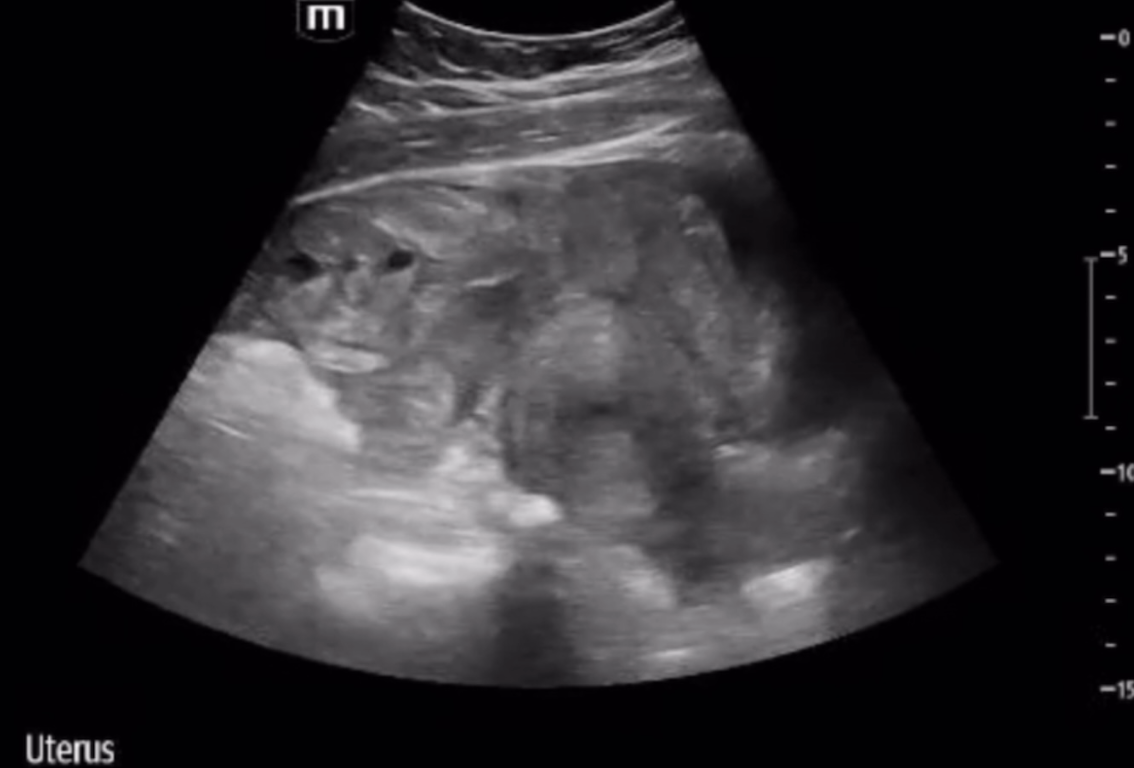

Here is a sagittal view of the pelvis, with bladder on the left. The uterus is more distinguishable here.

This is a still image of the above video clip. The uterus is easily visualized at a depth of 7 to 11 cm. Just superficial is the mixed echogenicity material. In the setting of hypotension you should suspect this is coagulated blood, and begin to do a FAST exam.

These findings are concerning for a ruptured ectopic pregnancy!!